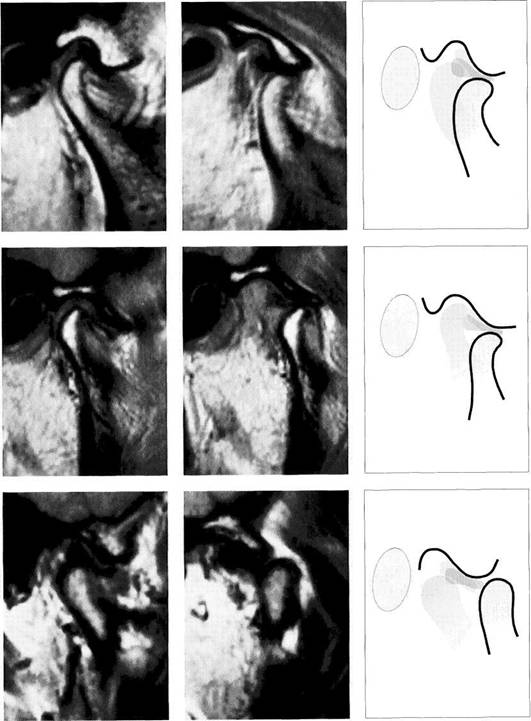

Physiological disk position

Under normal conditions, the pars intermedia (*) of the disk lies be­tween the anterosuperior curva­ture of the condyle and the articular protuberance (arrows). The posi­tion of the posterior border of the pars posterior relative to the vertex of the condyle varies according to the inclination of the protuberance and is therefore not a reliable pa­rameter.

The arrows in this schematic draw­ing mark the relative positions of the condyle and the pars interme­dia to one another.

Insidious disk displacement or a tendency to anterior disk displacement

The pars intermedia lies well in front of the shortest distance be­tween condyle and protuberance (arrows), but the pars posterior (1) still lies on the condyle. Clinically, there are no clicking sounds during jaw opening.

Right: Drawing of a joint with a ten­dency to anterior disk displace­ment. The arrows mark the discrep­ancy between pars intermedia and condyle.

Definite disk displacement

Left: Both the pars intermedia (*) and the posterior border of the pars posterior lie in front of the most anterosuperior curvature of the condyle (arrows). Unless this is a case of disk displacement without repositioning, a clicking sound will occur regularly during jaw opening.

Right: Schematic drawing of a defi­nite anterior disk displacement. The arrows mark the discrepancy between the pars intermedia and condyle.

Disk position in the frontal plane

Left: Schematic drawing illustrating normal disk position in the frontal plane.

Right: MRI of the right temporo­mandibular joint of a 24-year-old man. The frontal plane is angled so that it is parallel with the long axis of the condyle. With the jaws closed, the pars posterior of the disk is centered over the condyle.

Medial disk displacement

Left: Schematic drawing of a medial disk displacement in the frontal plane.

Right: MRI of the right temporo­mandibular joint of a 24-year-old patient. An adequate diagnosis of lateral and medial disk displace­ments cannot be made with arthrography and arthrotomogra-phy alone (Kurita et al. 1992a,b).

Lateral disk displacement

Left: Schematic drawing of a lateral disk displacement in the frontal plane.

Right: MRI of the right temporo­mandibular joint of a 23-year-old woman who sustained a fracture of the neck of the condyle at age 14 years. The condyle was tipped medially and has healed in an ab­normal position. The lateral disk displacement is causing pain and recurring limitation of jaw opening.